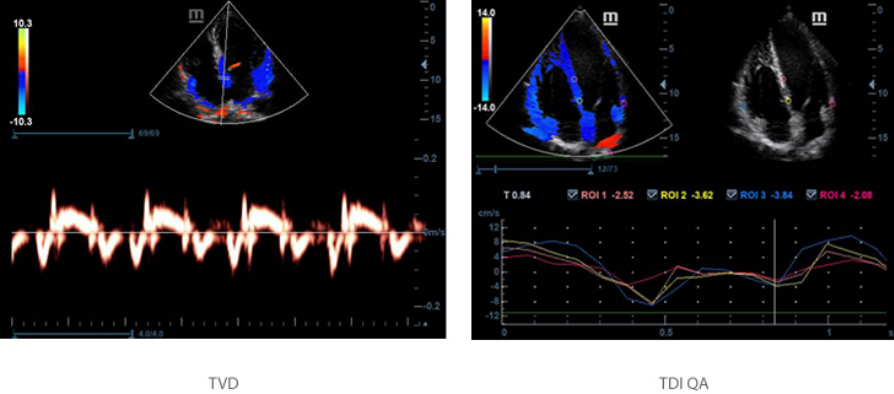

TDI & TDI QA

?? ??? ??(TDI)? ???? TDI QA? ??? ?? ?? ??? ?? ??? ?? ??? ? ??? ????? ??? ? ????.